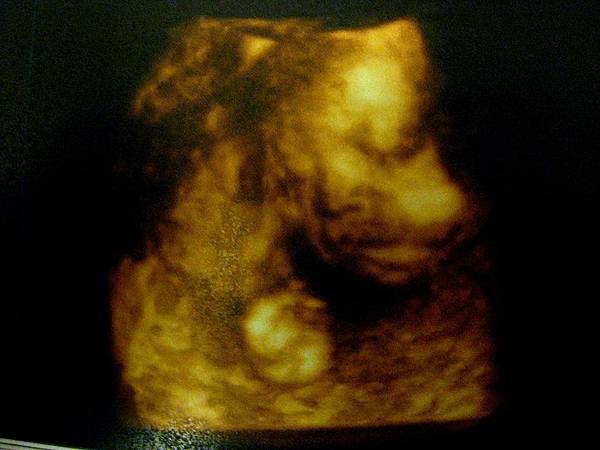

28週拍攝四D的糖果妹妹:

閉著眼睛,文文靜靜的模樣。